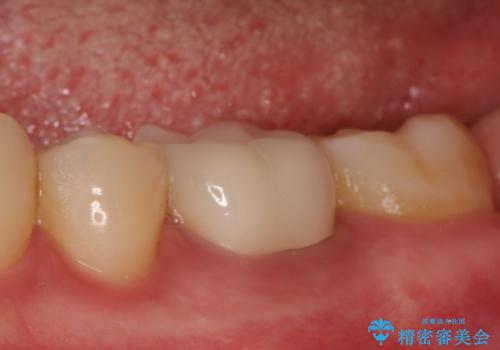

銀歯を除去し、セラミッククラウンに替えました。

審美性が良くなるだけでなく、拡大鏡を使用した治療、精度の高い材料の使用によって、虫歯の再発リスクを減らすことができます。